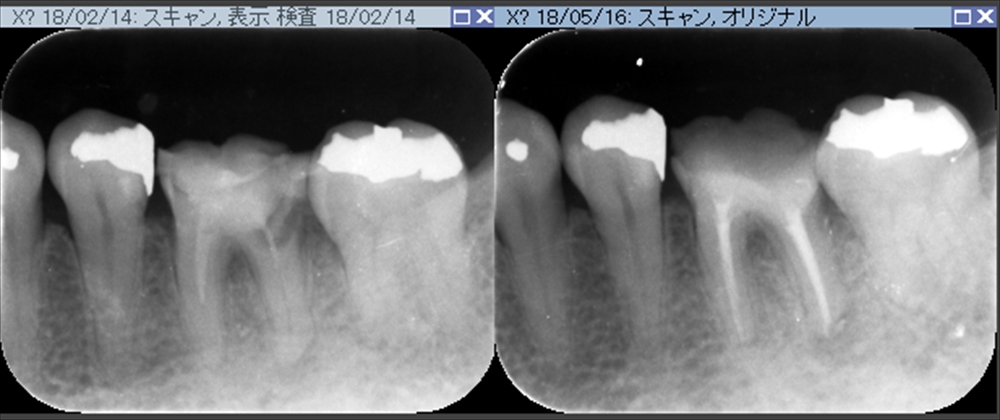

確かに虫歯は深く根管治療もしてあり石灰化もありそうな根管でした。でも歯科ドックの結果、抜歯せずに残せると診断しましたので

術前:左。術後:右

抜歯をせず治療が出来大変喜んで頂けました。

3回で根管治療終了。